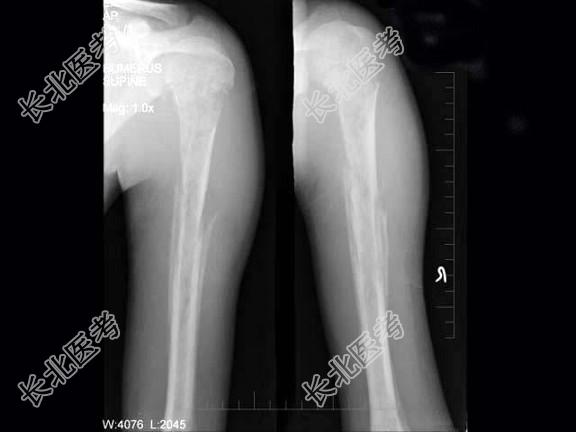

单项选择题男,15岁, 畏寒,高热2周, 摄片如图所示,下列诊断正确的是 ( )

A、急性化脓性骨髓炎

B、慢性化脓性骨髓炎

C、溶骨性骨肉瘤

D、尤文肉瘤

E、以上均不正确